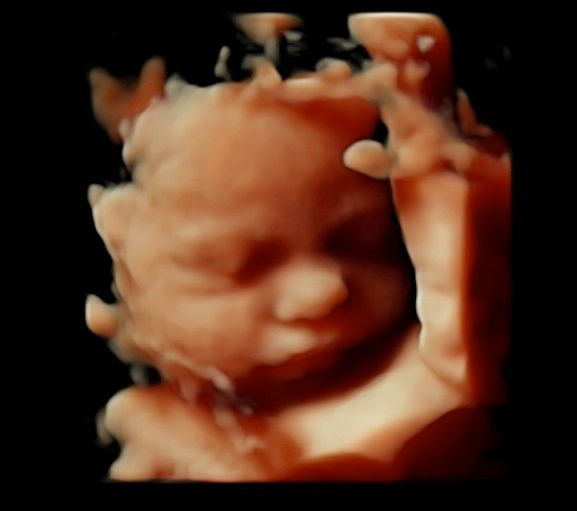

Foto e video